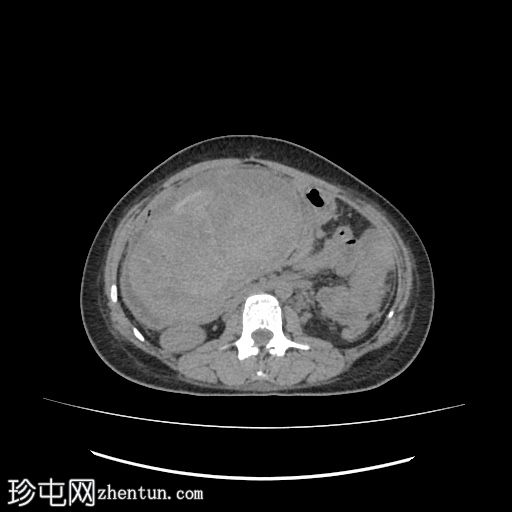

CT

轴位

平扫

肝下区可见一大小约15 x 15.2 x 8.6 cm的较大、边界清晰、呈不均匀强化的实性肿块。

该病灶压迫胃小弯、幽门和胃窦,并对肝脏产生占位效应。门静脉和下腔静脉受压,但脂肪间隙保持完整,未见明确的血管侵犯。

肿块左侧可见正常的胰尾。胰管未见扩张。

肝内胆管和胆总管管径正常。

腹主动脉旁可见亚厘米级淋巴结,最大者短轴直径为 3.5 mm。

中度弥漫性腹水,少量左侧胸腔积液。